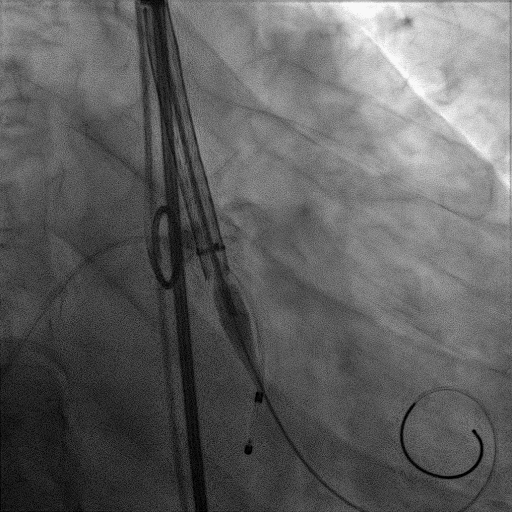

手术过程:

患者麻醉方式采取监护麻醉,建立静脉通路后,穿刺右侧股动脉预置两把Proglide缝合器。穿刺右侧股静脉,置入6F鞘管,将临时起搏器到位。经右股动脉行冠脉造影提示冠脉无有意义狭窄。加硬导丝送至左心室内,22mm球囊预扩张,Venus-A L26瓣膜精准定位并释放,后使用22mm球囊后扩张,瓣膜形态良好,结果满意。应用ProGlide缝合右股动脉穿刺部位并拔除临时起搏电极。术后患者即刻苏醒,安全返回普通病房。

主动脉根部造影

22mm球囊预扩张

Venus-A L26瓣膜精准定位

22mm球囊后扩张

瓣膜形态良好,结果满意